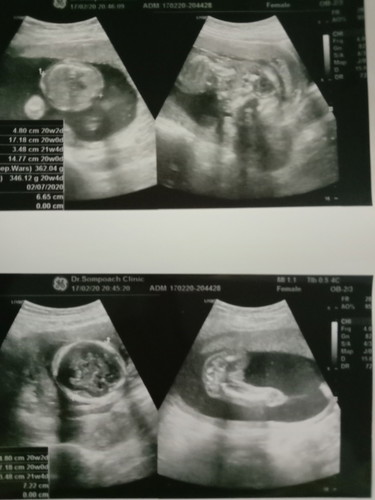

ดูไม่ออกว่า เพศ ญรึช ใครดูออกบ้างคะ

หมอบอกว่าเป็นเพศชาย แต่ยังไม่ชัวร์ ตอนนี้18w5dแล้วค่ะ กำหนดคลอด17ก.ค

บอกตามตรงว่าภาพไม่ชัดเลยค่ะแม่